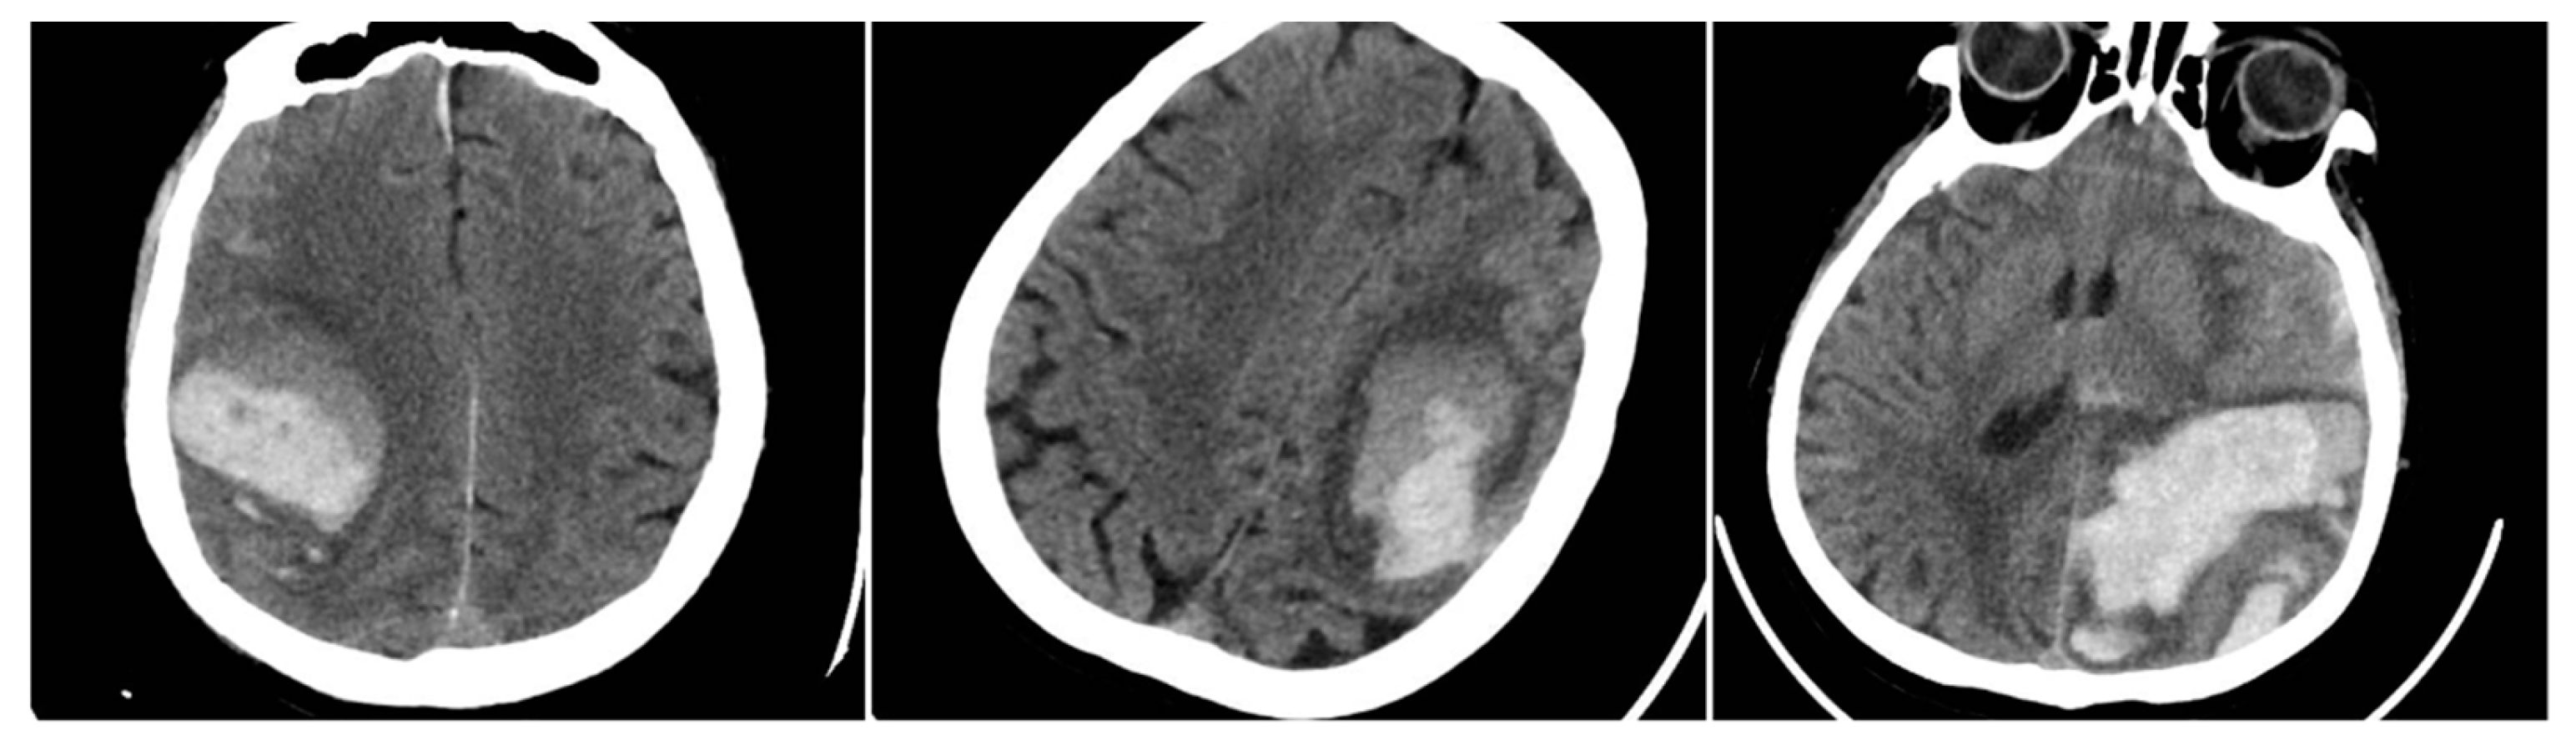

The Black Hole Sign (BHS) referred to a distinct hypodense area (≥28 HU difference) fully enclosed within a hyperdense clot (BHS=1 if present).

Figure 2. Black Hole Sign (BHS) – three examples from our cohort.

Irregular Shape (IRS) indicated a clearly lobulated or spiculated hematoma margin (IRS=1 if irregular, otherwise 0).

Figure 3. Irregular Shape sign – three examples from our cohort.

The Satellite Sign (SS) was identified when a small (≤10 mm) hyperdense hemorrhagic focus lay within 20 mm of, but separate from, the main clot on at least one CT slice (SS=1 if present). An aggregate score, SUM_BBIS (range 0–4), was computed by summing the presence of BS, BHS, IRS, and SS for each patient.

Figure 4. Satellite Sign (SS) – three examples from out cohort.